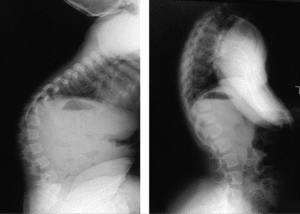

Kyphosis, characterised by an excessive curvature or hump in the back, is frequently observed in infants with achondroplasia due to their weak muscle tone and lax joints.

Typically, this condition resolves as the child begins walking and develops stronger core muscles.

Regular X-rays may be ordered by your child’s healthcare provider to monitor the progression of the curvature.

If the curve does not improve over time, children may need to wear a back brace to prevent further curvature or undergo corrective surgery.

The X-ray image on the left displays a kyphotic curve in the upper back of a child diagnosed with achondroplasia. On the right side, it can be observed that the curve has spontaneously corrected itself over time, a typical occurrence in children with achondroplasia.